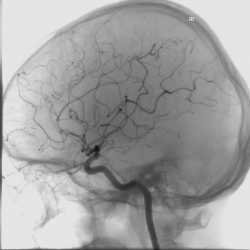

- 혈관 조영술 : 혈관 상태와 협착 여부를 파악할 수 있습니다.

- 약물 치료 : 혈전 용해제(rtPA)를 사용하여 혈류를 회복

- 수술적 치료 : 혈관 내 시술로 막힌 혈관을 열어주는 방법